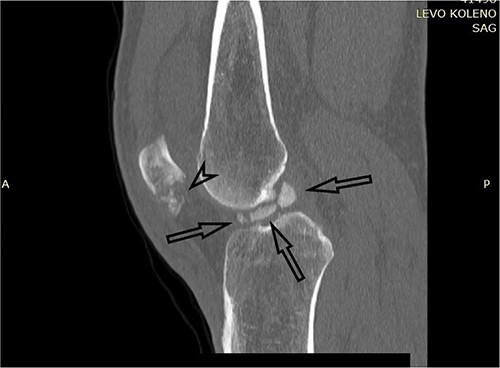

A plain X-ray of the left knee revealed a single defect of the lateral femoral condyle in the anteroposterior (AP) view. The lateral view showed a free bone fragment with a defect (Fig. 1A and B). Additional diagnostic imaging was performed. A computerized tomography (CT) scan revealed multifragmentary (three fragments) fracture of the lateral femoral condyle accompanied by a fracture of the left patella (Fig. 2). The fracture was classified as 33B3.2 according to the Association for Osteosynthesis–Orthopaedic Trauma Association (AO/OTA), Type II C (according to Letenneur) [2]. It was decided that single-approach surgery (posterior or anterior) would be insufficient for acceptable anatomic reduction and proper fixation of all the fragments because of the fracture complexity. The preoperative plan consisted of a posterior-first approach (extended posterior approach to the proximal tibia) for fixation of the largest (posterior) fragment (Fig. 3) followed by an arthroscopic anterior approach (for anterior fragment fixation). The predetermined time interval between the two procedures was to allow the healing of the joint capsule after the index surgery. Operative fixation of the patellar fracture was not indicated.

CT scan of the left knee (sagittal) with three fragments (arrows) and patellar fracture (arrowhead).